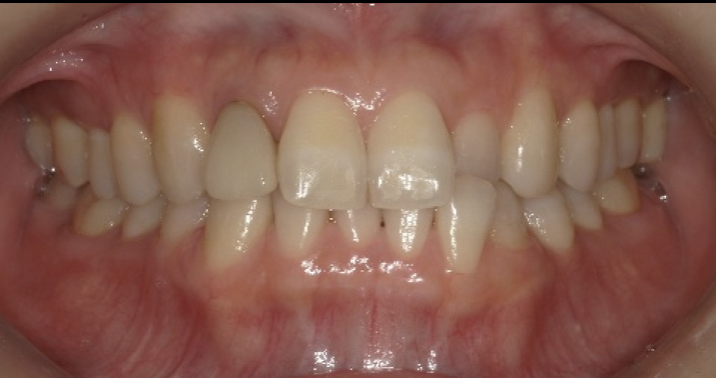

池袋で前歯のすき間をダイレクトボンディングで改善した症例|正中離開を削らずに自然に修復

- 主訴

- 前歯のすき間が気になる

見た目を自然に整えたい

- 1回

- 11万

- 前歯2本に対するダイレクトボンディング

・経年的な着色が起こることがあります

・強い衝撃や咬み合わせによって欠けることがあります

・すき間の大きさや咬み合わせによっては、矯正治療や他の補綴治療が適する場合があります

・定期的なメインテナンスが必要です